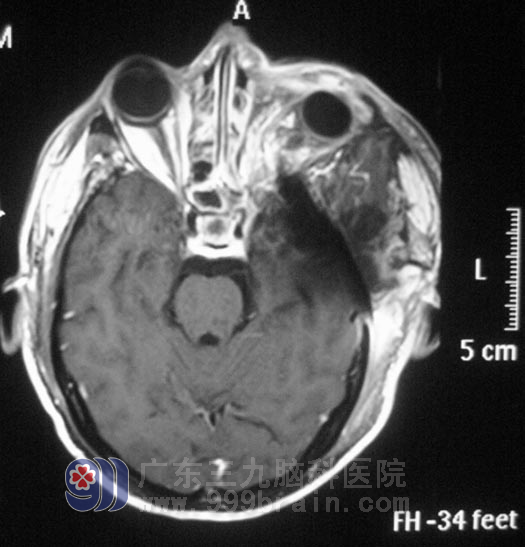

经过治疗,他的左侧眼球回缩,头痛症状明显好转,已顺利出院。

▲手术后